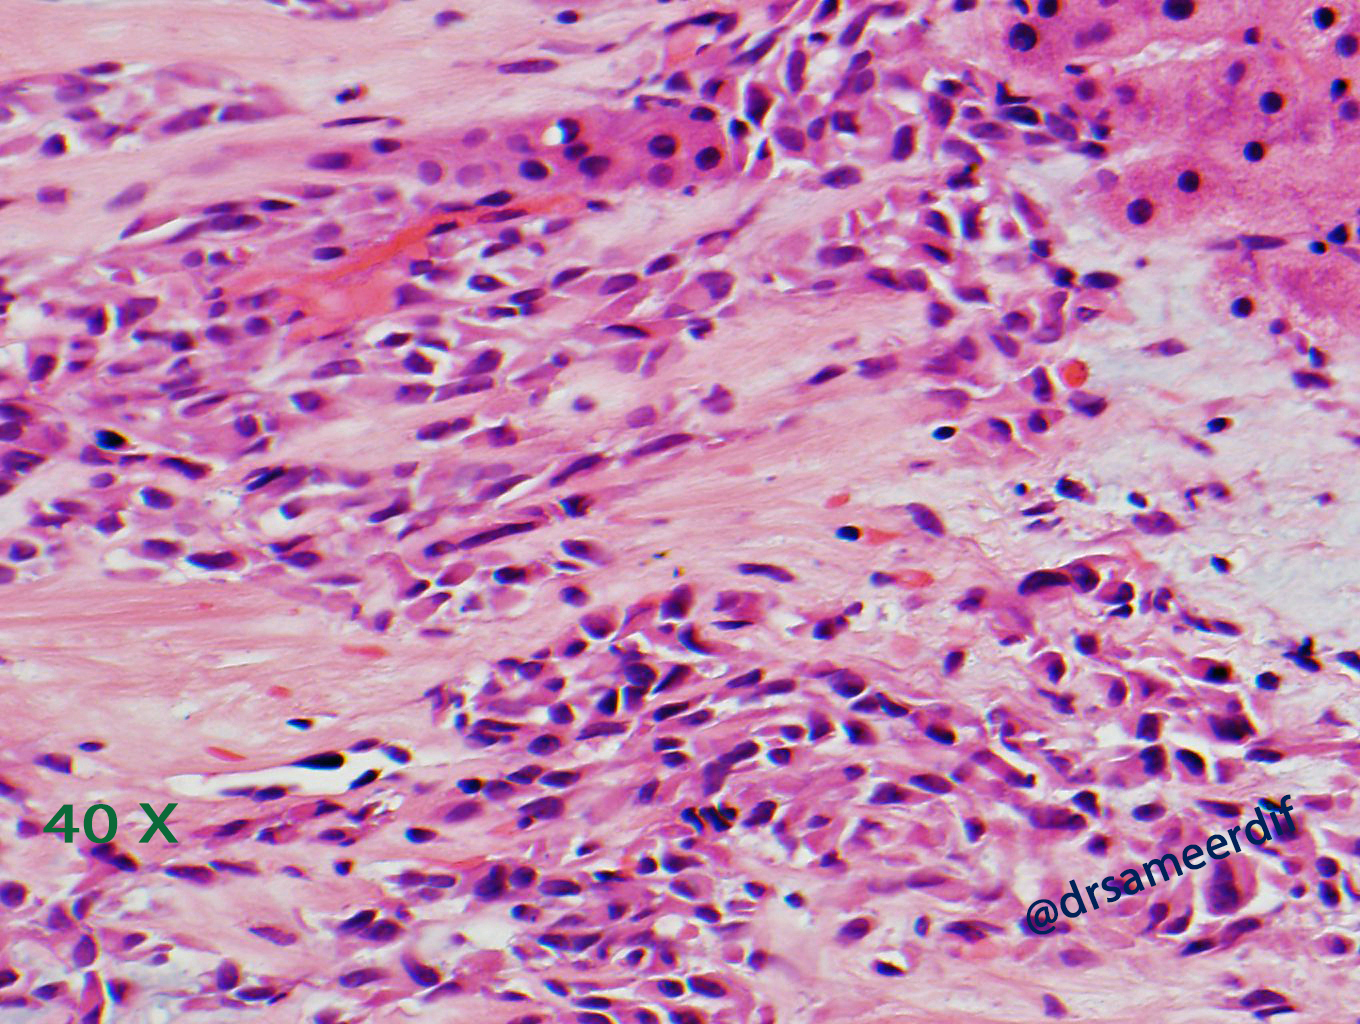

The current biopsy shows a densely hyalinized sclerotic matrix, with focal areas reminiscent of osteoid, lined by small to medium-sized epithelioid cells with clear to eosinophilic cytoplasm and bland nuclei. Mitotic figures are inconspicuous. By immunohistochemistry, the neoplastic cells are positive for MUC4, but negative for CK7, CK20, SATB2, and calcitonin. The morphology and immunohistochemical results are diagnostic of metastatic sclerosing epithelioid fibrosarcoma (SFE) from primary know SFE of the soft tissue.

- Nests and cords of small to medium size, round- oval nuclei with scant clear to pale cytoplasm

- Hyalinized stroma, which may resemble osteoid. Sometimes cartilaginous and osseous metaplasia may be seen and it may show focal myxoid change or calcification.